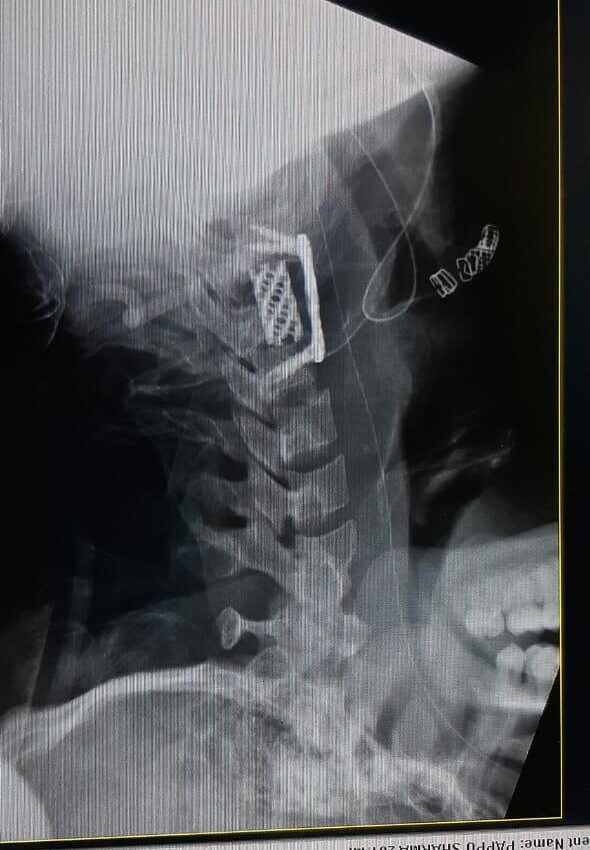

Moments That Mark Meaningful Recovery

Witness real patient transformations at The Ortho Clinic through images that reflect successful treatments and restored mobility.